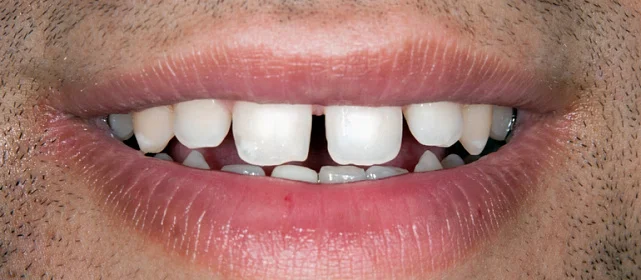

Скученность зубов, обе челюсти сужены — зубам не хватало места в ряду.

Проблема: Пациентка обратилась с одной жалобой — неровные зубы. При осмотре обнаружили, что обе челюсти сужены, зубам банально не хватает места, отсюда скученность. Зубы здоровые, ортопедия не нужна — чисто ортодонтический случай.

Брекет-система на обе челюсти. Расширить зубные дуги и убрать скученность. Срок — около 1,5 лет.